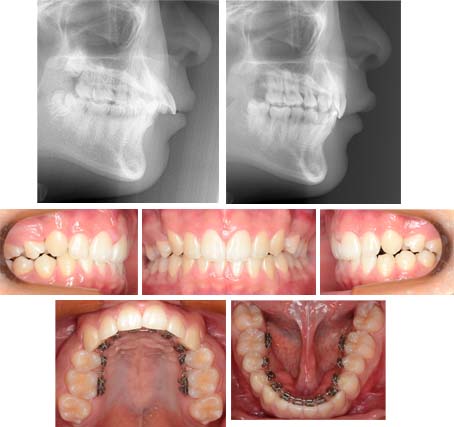

治療例 No. 325 上顎前突 深い噛み合わせ

来院時の写真

気になっている点(主訴): 上顎前突 出っ歯

前方から下顎前歯の存在を確認する事ができません。かなり厳しい上顎前突です。リンガルブラケットで治療開始です。

治療中の写真

上顎第一小臼歯を抜歯しました。噛み合わせをしっかり上方にあげました。治療は成功しました。リンガルブラケットはこういった厳しい上顎前突は得意にしています。アンカースクリュウは使用していません。必要ありませんでした。最近はこれぐらいの症例はブラケットを着けている期間が2年かからない事が多いです。

上顎前歯の前方傾斜、下顎前歯の挺出による上顎前突です。下顎前歯は上顎の粘膜とかみ合っていました。

抜歯部位 : 上顎左右第一小臼歯

治療に使用した装置 : リンガルブラケット

上顎前歯を内側に移動して来ました。治療後のレントゲン写真から歯根吸収は認められませんでした。

治療期間 : 21か月